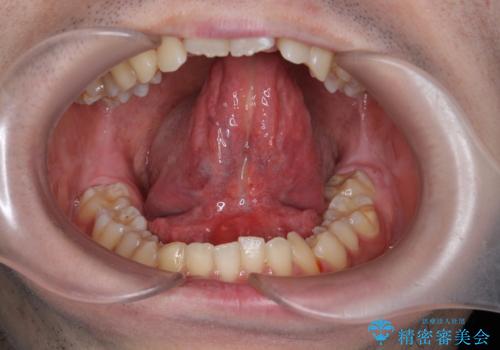

滑舌の改善 舌小帯の形成

舌小帯の形成を行うことで、動きがよくなり滑舌の改善を喜んでいただくことができました。

小手術に際して、少量の出血・疼痛のリスクがあります。